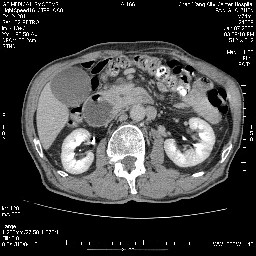

女,74岁,呕吐10余日

十二指肠水平段腔内占位伴梗阻,中等度较为均匀的强化,洗脱慢,区域淋巴结显示增多,符合腺癌表现。下腔静脉变异。

十二指肠降段扩张,水平段狭窄成鼠尾状,肠壁明显增厚,胰腺勾突增大成不均匀强化,其内可见低密度区,胆囊增大,1十二指肠水平段腺癌侵犯胰腺勾突可能大,2胰腺癌侵犯十二指肠(只有胆囊增大没有肝内外胆管扩张不好解释)代除外.

上消化道造影见十二指肠结节状充盈缺损,ct增强十二指肠壁局限性增厚并强化,考虑十二指肠壶腹癌?

十二指肠降段扩张,水平段狭窄成鼠尾状,肠壁明显增厚,胰腺勾突增大成不均匀强化,其内可见低密度区,胆囊增大,1十二指肠水平段腺癌侵犯胰腺勾突可能大,2胰腺癌侵犯十二指肠 。

今日手术结果:胰腺钩突癌侵犯十二直肠,腹腔淋巴结转移.